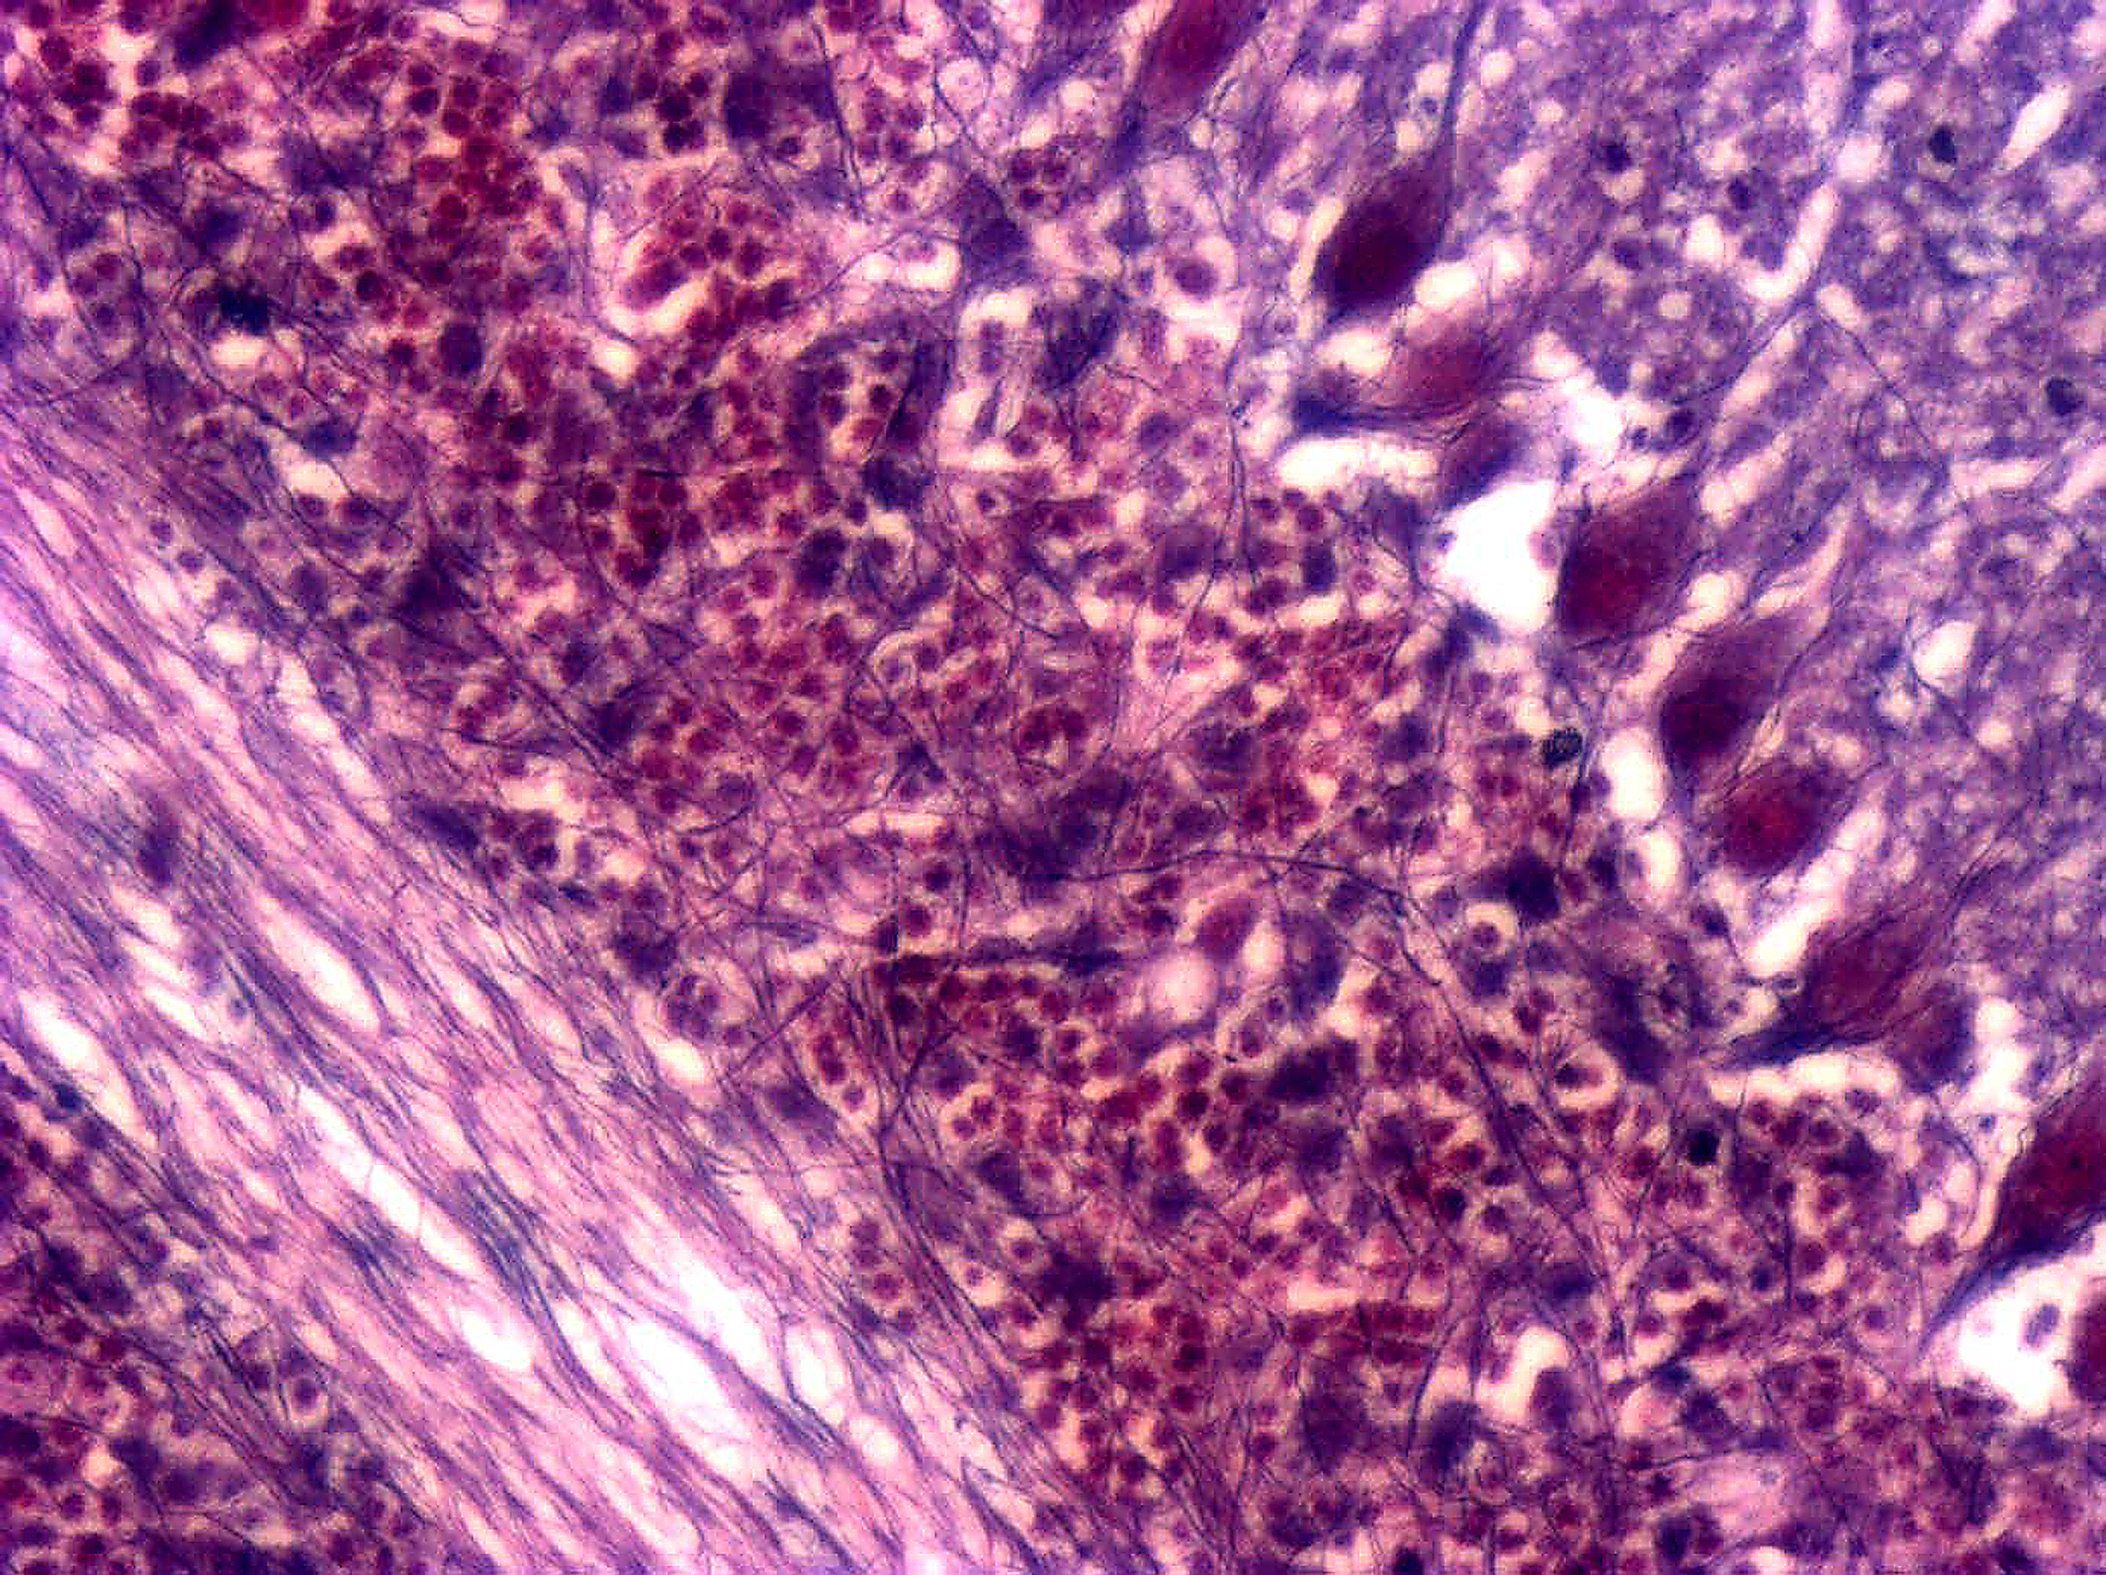

Cellules de Purkinje de cervelet de souris (X40)

Coloration de Holmes